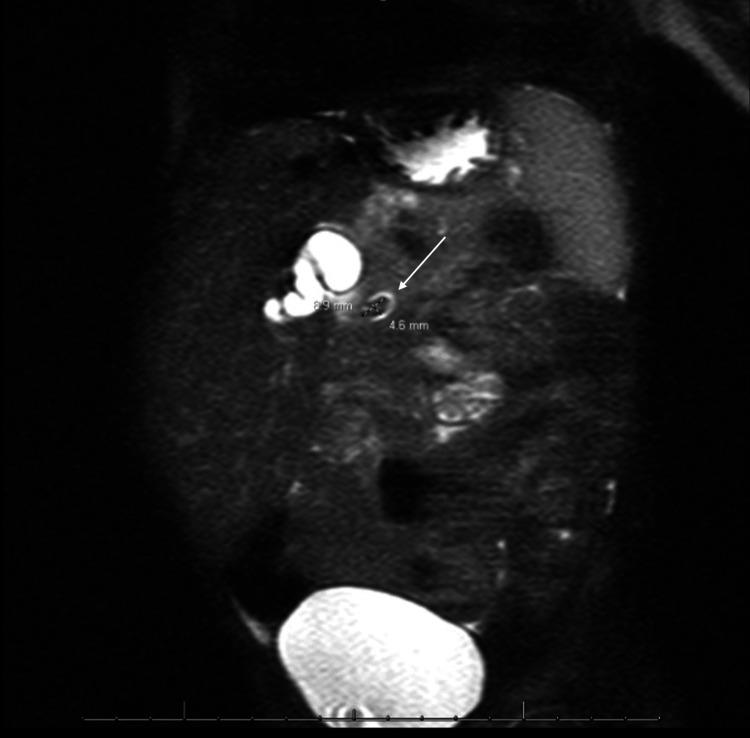

Cholelithiasis, or gallstone(s), is a leading cause of healthcare utilization in the United States. It is more common in adults but can occur in the pediatric population as well. The following is a case report of choledocholithiasis in a 19-month-old girl. A 19-month-old girl with abdominal pain presented to the emergency department (ED) after being found to have cholelithiasis on an outpatient abdominal ultrasound (US). Three days prior to presentation, the patient was seen by her pediatrician for fussiness, decreased oral intake, and non-bloody, non-bilious emesis. She was diagnosed with a suspected urinary tract infection (UTI) and prescribed amoxicillin-clavulanate for empiric treatment. The following day, the patient returned to her pediatrician for worsening abdominal pain; she was given one dose of intramuscular ceftriaxone and scheduled for outpatient abdominal US. Her past medical history is significant for omphalocele status post-surgical correction, several congenital cardiac defects, bilateral small kidneys, and poor weight gain. The patient has a normal chromosomal microarray and no family history of hepatobiliary/pancreatic disease. In the ED, the patient was afebrile and hemodynamically stable. Physical examination was significant for mild hepatomegaly, mild abdominal tenderness without peritoneal signs, and the presence of a well-healed surgical scar on the abdomen with an underlying abdominal hernia. Laboratory tests were significant for leukocytosis of 14.5×10/microliter (mcL), elevated gamma-glutamyl transferase (GGT) of 305 unit/L (U/L), aspartate aminotransferase (AST) of 86 U/L, alanine aminotransferase (ALT) of 343 U/L, total bilirubin of 2.3 milligram/deciliter (mg/dL), direct bilirubin of 1.6 mg/dL, and lipase of 1,726 U/L. Abdominal US revealed several gallstones and mild to moderate intra- and extrahepatic biliary ductal dilatation likely due to a stone in the distal common bile duct (CBD). Pediatric surgery and gastroenterology recommended admission for pain management and magnetic resonance cholangiopancreatography (MRCP). After admission, the patient was started on ursodiol and piperacillin/tazobactam. MRCP showed a common hepatic duct measuring 13 mm and a 9×5 mm stone in the distal common bile duct. Due to a lack of available outside facilities with the capability to perform endoscopic retrograde cholangiopancreatography (ERCP) in a pediatric patient, medical management was pursued. Throughout her admission, the patient improved clinically, laboratory studies became normal, and pain was controlled. Repeat US showed persistent biliary dilation with cholelithiasis. The patient was cleared for discharge on ursodiol and amoxicillin-clavulanate and close follow-up with pediatrician, pediatric surgeon, and pediatric gastroenterologist. Follow-up US performed two weeks after discharge showed interval resolution of intra- and extrahepatic biliary duct dilatation and cholelithiasis without evidence of cholecystitis. Abdominal pain accounts for 5%-10% of all pediatric ED visits, and although cholelithiasis and choledocholithiasis are rare in the pediatric population, as this case demonstrates, it is an important differential diagnosis. Observation is the recommended management for asymptomatic patients as most cases spontaneously resolve. Patients with clinical signs or laboratory abnormalities can be treated medically, with ERCP, or with cholecystectomy.

胆石症,即胆结石,是美国医疗资源利用的主要原因之一。它在成年人中更为常见,但也可能发生在儿童群体中。以下是一例19个月大女童胆总管结石的病例报告。一名19个月大的腹痛女童在门诊腹部超声检查发现胆结石后前往急诊科就诊。就诊前三天,患儿因烦躁、口服摄入量减少以及非血性、非胆汁性呕吐被儿科医生诊治。她被诊断为疑似尿路感染,并开具阿莫西林 - 克拉维酸进行经验性治疗。第二天,患儿因腹痛加剧再次前往儿科医生处;她接受了一剂肌内注射头孢曲松,并安排进行门诊腹部超声检查。她既往病史包括脐膨出手术后矫正、多种先天性心脏缺陷、双侧小肾脏以及体重增加缓慢。患儿染色体微阵列正常,且无肝胆/胰腺疾病家族史。在急诊科,患儿体温正常,血流动力学稳定。体格检查发现轻度肝肿大、轻度腹部压痛但无腹膜刺激征,腹部有愈合良好的手术瘢痕及潜在的腹壁疝。实验室检查显示白细胞计数为14.5×10/微升(mcL),γ-谷氨酰转移酶(GGT)升高至305单位/升(U/L),天冬氨酸氨基转移酶(AST)为86 U/L,丙氨酸氨基转移酶(ALT)为343 U/L,总胆红素为2.3毫克/分升(mg/dL),直接胆红素为1.6 mg/dL,脂肪酶为1726 U/L。腹部超声显示多个胆结石以及轻至中度肝内外胆管扩张,可能是由于胆总管远端结石所致。儿科外科和胃肠病学建议住院进行疼痛管理并进行磁共振胰胆管造影(MRCP)。入院后,患儿开始使用熊去氧胆酸和哌拉西林/他唑巴坦。MRCP显示肝总管直径为13毫米,胆总管远端有一颗9× 5毫米的结石。由于缺乏能够对儿科患者进行内镜逆行胰胆管造影(ERCP)的外部设施,因此采取了药物治疗。在整个住院期间,患儿临床症状改善,实验室检查结果恢复正常,疼痛得到控制。复查超声显示仍有持续的胆管扩张及胆结石。患儿出院时带药熊去氧胆酸和阿莫西林 - 克拉维酸,并安排与儿科医生、儿科外科医生和儿科胃肠病学家密切随访。出院两周后进行的随访超声显示肝内外胆管扩张及胆结石均有改善,且无胆囊炎迹象。腹痛占所有儿科急诊就诊病例的5% - 10%,尽管胆石症和胆总管结石在儿科人群中罕见,但正如本病例所示,它是一个重要的鉴别诊断。对于无症状患者,建议进行观察,因为大多数病例可自行缓解。有临床症状或实验室异常的患者可进行药物治疗、ERCP或胆囊切除术。